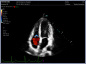

Neben einem ausführlichen Gespräch, der Anamnese, Zeit und Zuwendung gehören auch die Anwendung von wissenschaftlich evaulierten diagnostischen Verfahren zu einer guten Eingangsuntersuchung. Ich freue mich Ihnen in meiner Praxis deshalb nun auch die Ultraschalluntersuchung mit modernster Technik, einem mindray Consona N6 anbieten zu können.

- Darstellung der Schilddrüse - Darstellung der hirnversorgenden Gefäße mit Messung der Intimadicke (IMD) - Ultraschall des Herzens z. B. Stenose / Dichtigkeit der Herzklappen, Wandbewegungsstörungen,... - Ultraschall des Bauchraumes wie Leber, Gallenblase, Nieren, Blase, Milz. - Gefäßdarstellung

Video Farbdoppler der Halsarterie zur Darstellung der Durchblutung Video Farbdoppler der Niere zur Darstellung der Durchblutung Video Herzultraschall eines gesundes Herzens mit guter Pumpfunktion Video Herzultraschall mit eingeschränkter Pumpfunktion und vergrößerten Vorhöfen Video Herzultraschall bei Herzinsuffizienz und undichter Herzklappe